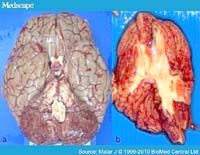

Xét nghiệm máu ngoại vi của bệnh nhân nhiễm P. knowlesi có thể được chẩn đoán nhầm là nhiễm P. malariae, do có sự tương đồng về mặt hình thái giữa 2 loài Plasmodium này. Do vậy, nhiễm P. knowlesi có nhiều khả năng có các biểu hiện lâm sàng giống như P. malariae hoặc ở bệnh nhân sốt rét nặng xuất hiện hình thái giống P. malariae trên lam máu ngoại vi. Hay nói đúng hơn, một điểm chúng ta cần lưu ý là nếu hình thái trên lam giống P. malariae nhưng triệu chứng biểu hiện nghiêm trọng, thì nên nghĩ đến loài P. knowlesi và cần có các bước tiếp theo.